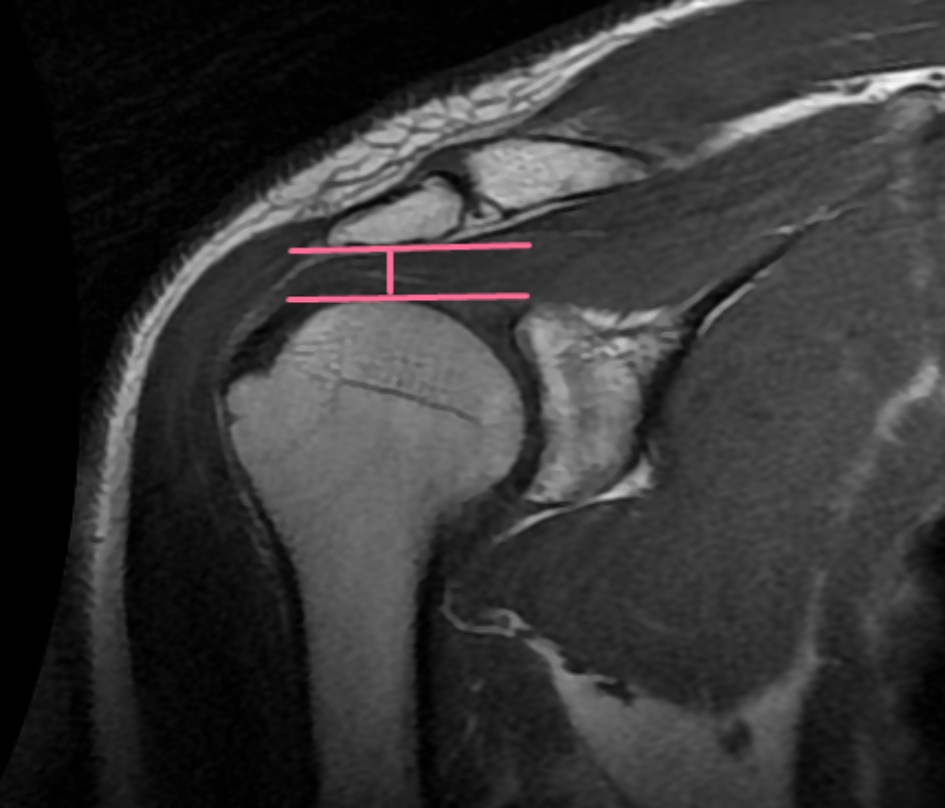

1) 参照Moor等人[3]的描述,进行CSA的测量(见图1):

在斜冠状位T1WI图像上,首先找到关节盂中心层面,并连接关节盂上下缘做一直线;然后,识别肩峰的最外侧点并用鼠标光标标记;最后,测量关节盂上缘到下缘连线与关节盂下缘到肩峰最外侧点连线之间的夹角。

Figure 1. Shows the method for measuring cross-sectional area (CSA) on MRI images

1. MRI图像测量CSA方法